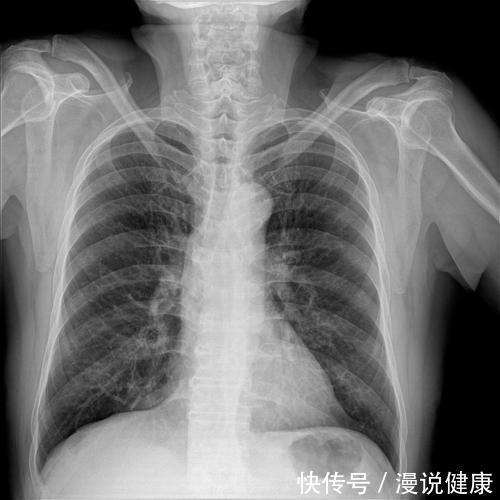

肺癌是发病率和死亡率增长最快,且对人生命威胁最大的恶性肿瘤之一。根据数据统计显示近50年来,肺癌的发病率和死亡率都在不断上升。

而迄今为止,导致肺癌发作的病因依然不是完全明确,尽管大量临床数据显示,肺癌的发作和长时间吸烟有着密切的关系。

文章插图

但这并不意味着,吸烟是导致肺癌发作的唯一原因。其实,肺癌的出现往往和以下几个因素也有关系。